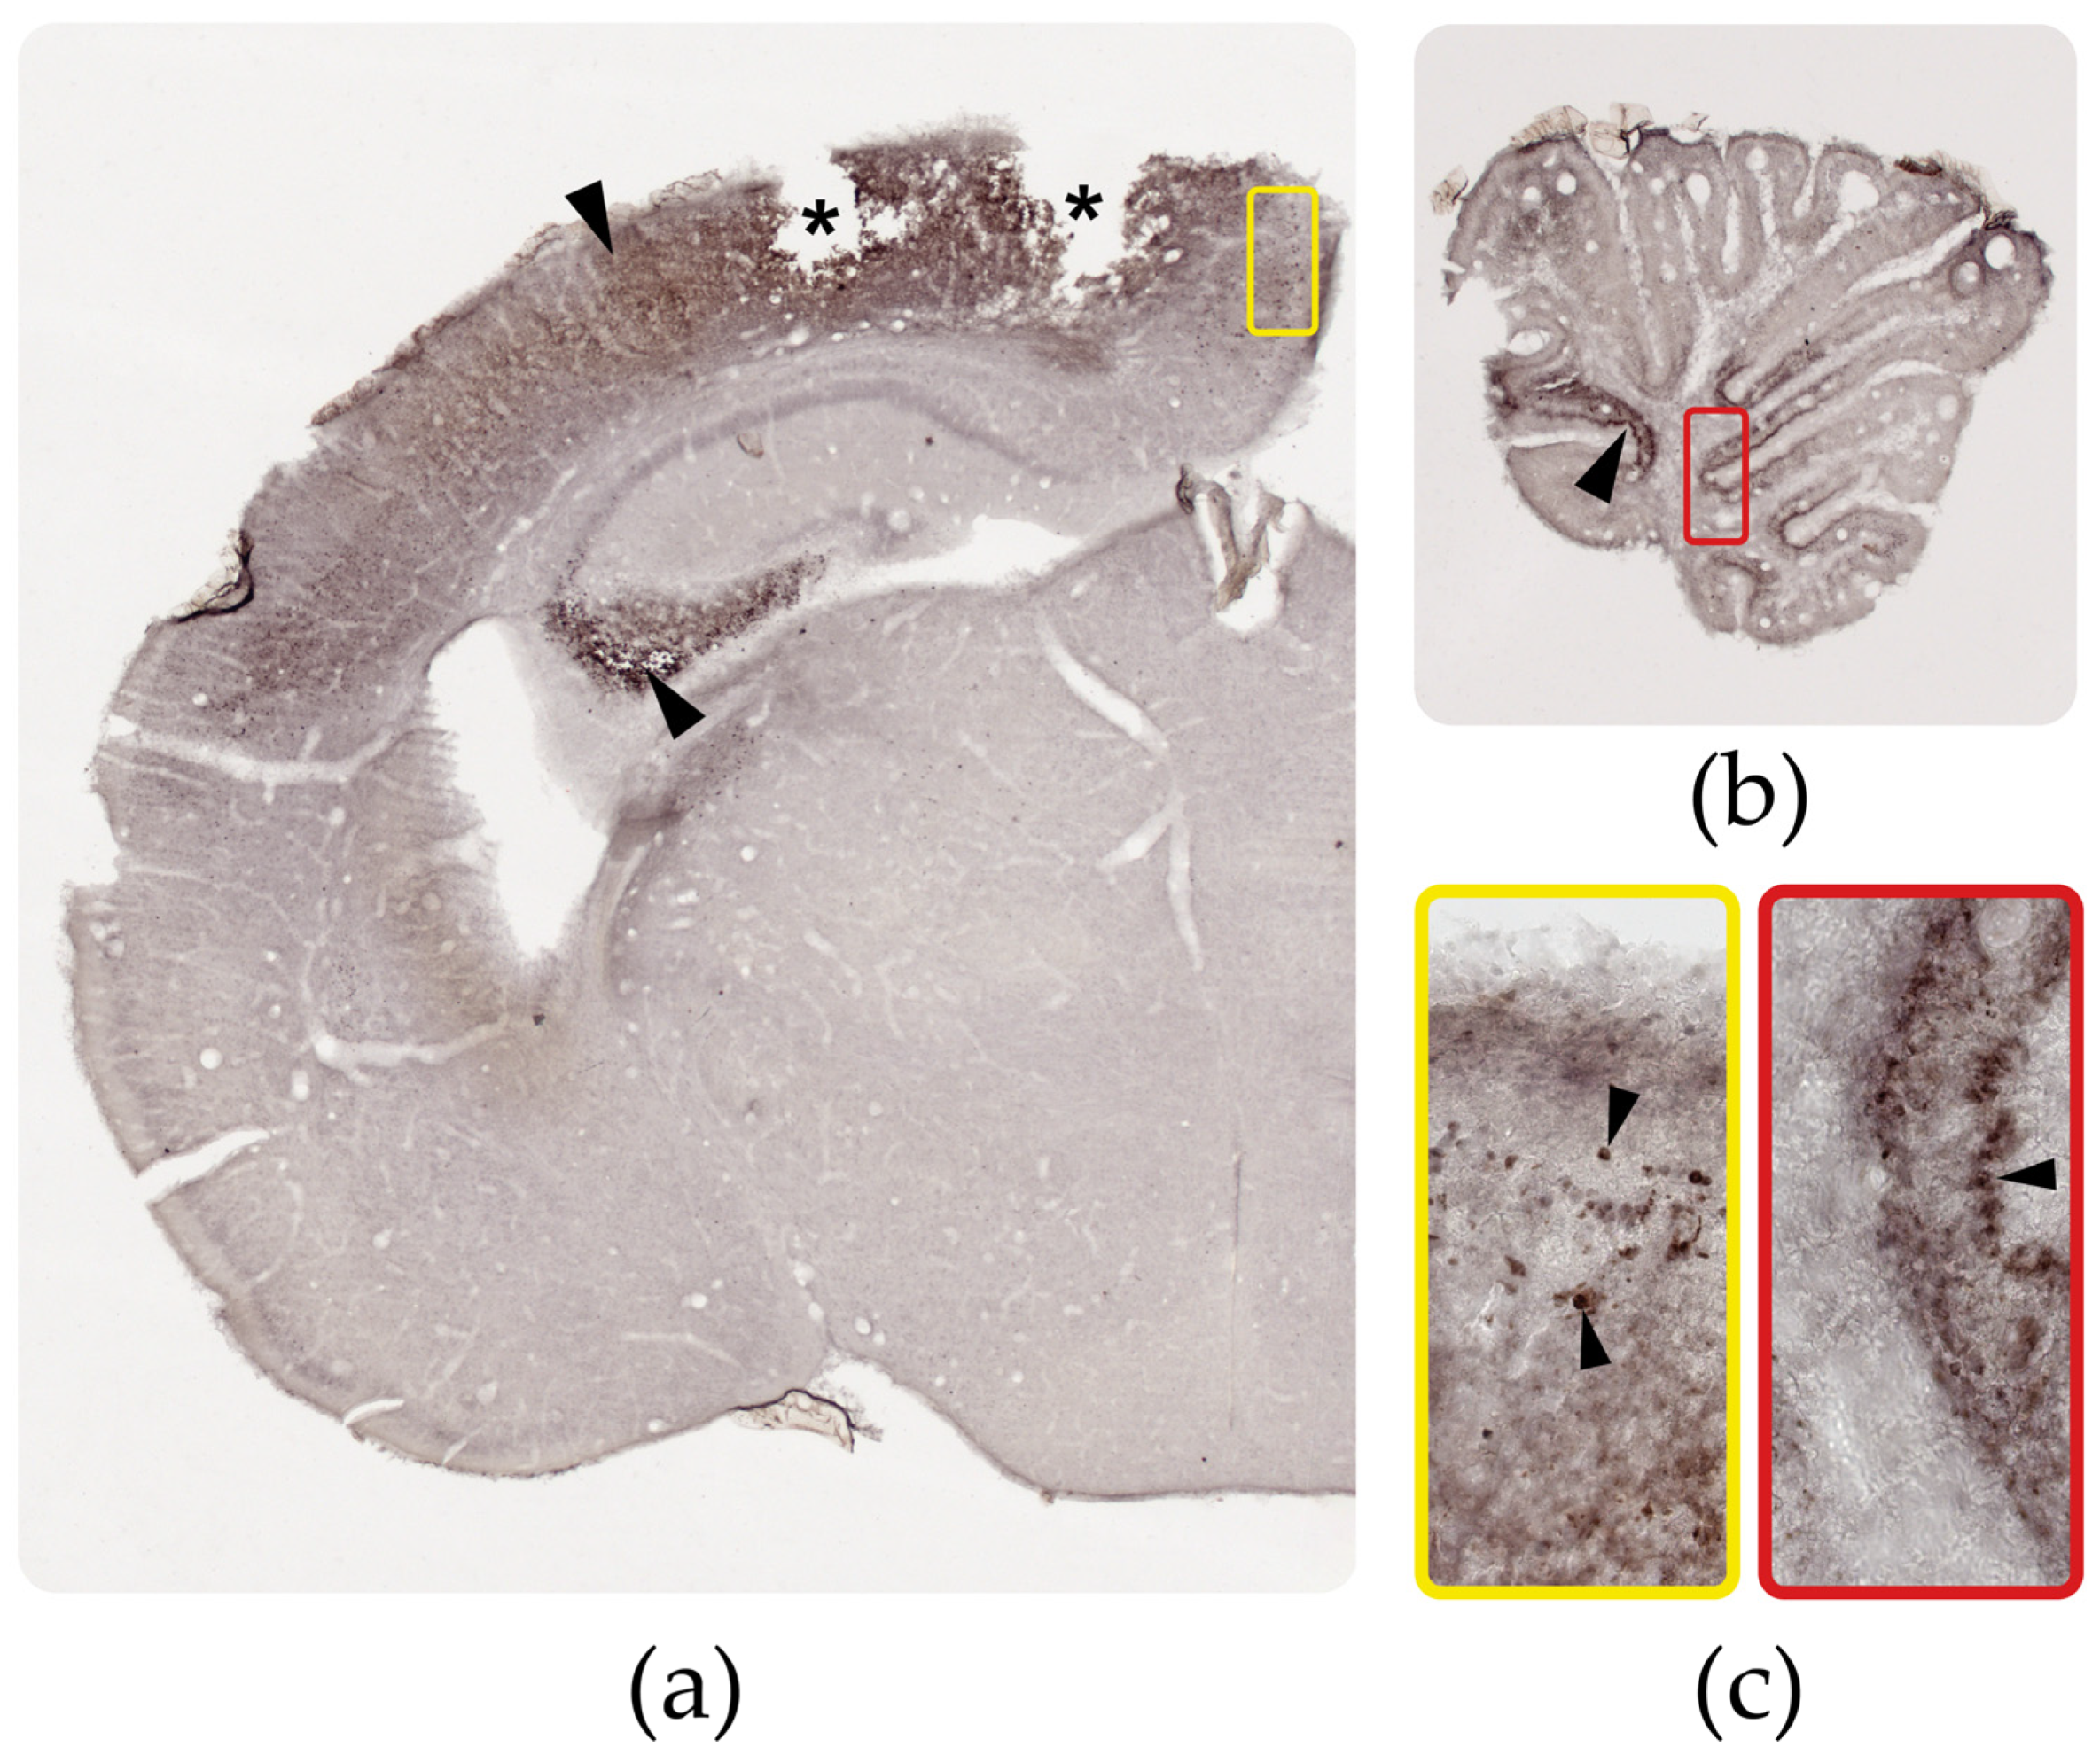

3.3. Distribution of the ZIKV Antigen, Genome, and Viral Load